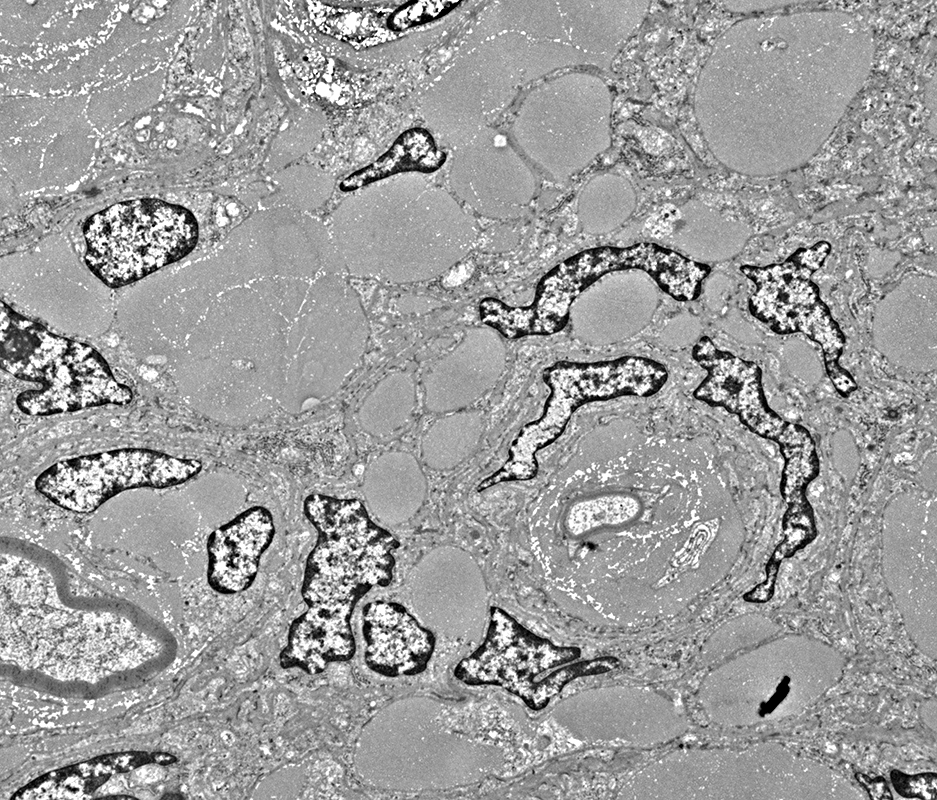

Perineurioma

From: R Schmidt

Perineurial cells

Irregular elongated nuclei in perimysium, often near collagen pockets

Myelinated axon

Surrounded by region containing mainly collagen

Collagen pockets

Many in endoneurium

Unmyelinated axons

Immediately surrounded by thin Schwann cell process: Stains for

MBP, not

NCAM

Within regions containing mainly collagen